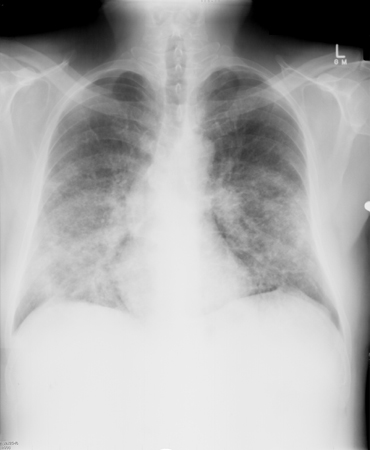

ფილტვის კრიპტოკოკოზის რადიოლოგიური ნიშნები ფართოდ ვარირებს პაციენტის იმუნური მდგომარეობის შესაბამისად და მოიცავს კვანძებს, კონსოლიდაციას, კავიტაციას, წილოვან ინფილტრაციაა, ჰილარულ ლიმფადენოპათიას, შუასაყრის ლიმფადენოპათია, პლევრული ეფუზია და კოლაფსი. იმუნოკომპეტენტურ პაციენტებში ვლინდება დისკრეტული კვანძები, ხოლო ალვეოლური და ინტერსტიციული ინფილტრატები, კავიტაციები, პლევრის დაავადება და კოლაფსი უფრო ხშირად აღინიშნება იმუნოკომპრომისულ პაციენტებში.[1][4][44][45][Figure caption and citation for the preceding image starts]: ორმხრივი ზარბაზნის ბირთვისებრი დაზიანებები, გამოწვეული Cryptococcus neoformans-ის მიერრადიოლოგიის დეპარტამენტის კოლექციიდან, The Prince Charles Hospital, Chermside, Brisbane, Australia; გამოიყენება ნებართვით [Citation ends].